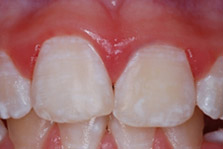

Figure 2. Prevalence of DF in the United States, 1999-2004

In the United States, DF is generally very mild or mild.5Beltrán-Aguilar ED, Barker Lk, Canto MT, Dye BA, Gooch BF, et al. Surveillance for Dental Caries, Dental Sealants, Tooth Retention, Edentulism, and Enamel Fluorosis --- United States, 1988--1994 and 1999--2002. MMWR 2005;54(03):1-44. Based on the National Health and Nutrition Examination Survey (NHANES), 1999–2004, 40.7% of adolescents 12 to 15 years-of-age experienced DF.5Beltrán-Aguilar ED, Barker Lk, Canto MT, Dye BA, Gooch BF, et al. Surveillance for Dental Caries, Dental Sealants, Tooth Retention, Edentulism, and Enamel Fluorosis --- United States, 1988--1994 and 1999--2002. MMWR 2005;54(03):1-44. Very mild and mild DF was present in 28.5% and 8.6% of adolescents, respectively, and moderate to severe DF in 3.6% of individuals. (Figure 2) A prevalence of less than 1% was found for severe DF.6Beltrán-Aguilar ED, Barker L, Dye BA. Prevalence and severity of dental fluorosis in the United States, 1999-2004. NCHS Data Brief 2010;(53):1-8.